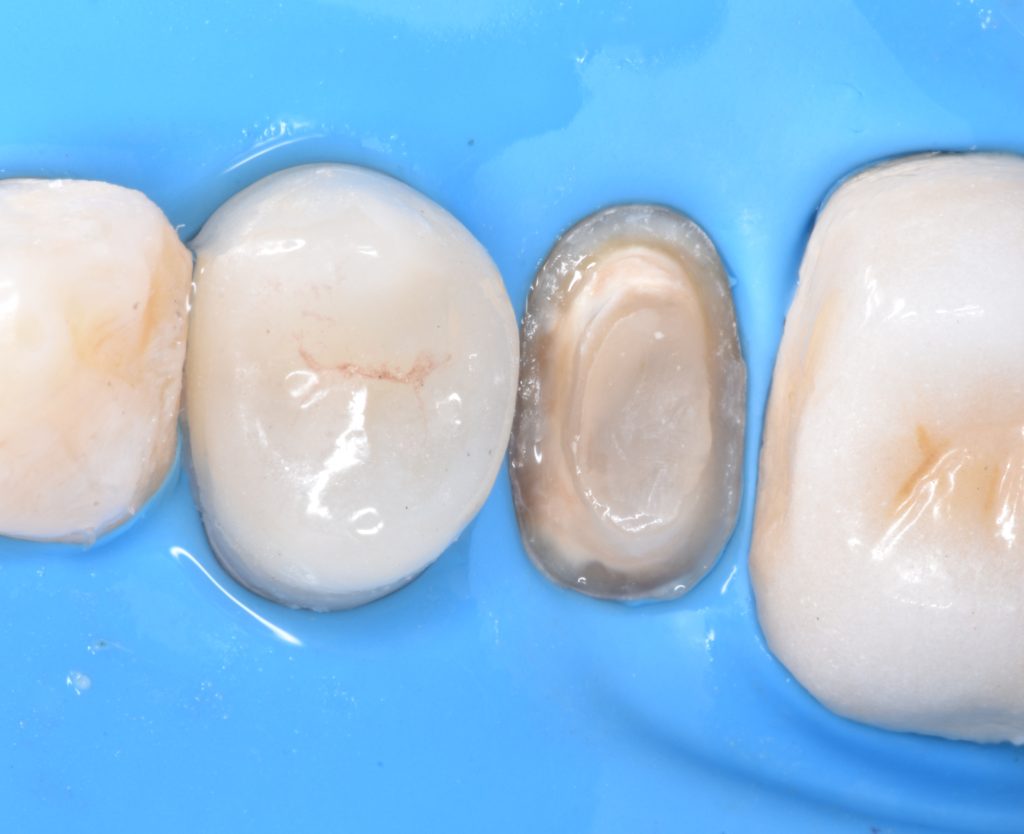

Caries removal with aid of caries detector dye

Deep margin elevation using circumferencial Copper bands

Elevation by snow plow technique n

And final design to receive to monolithic lithium disilicate restorations